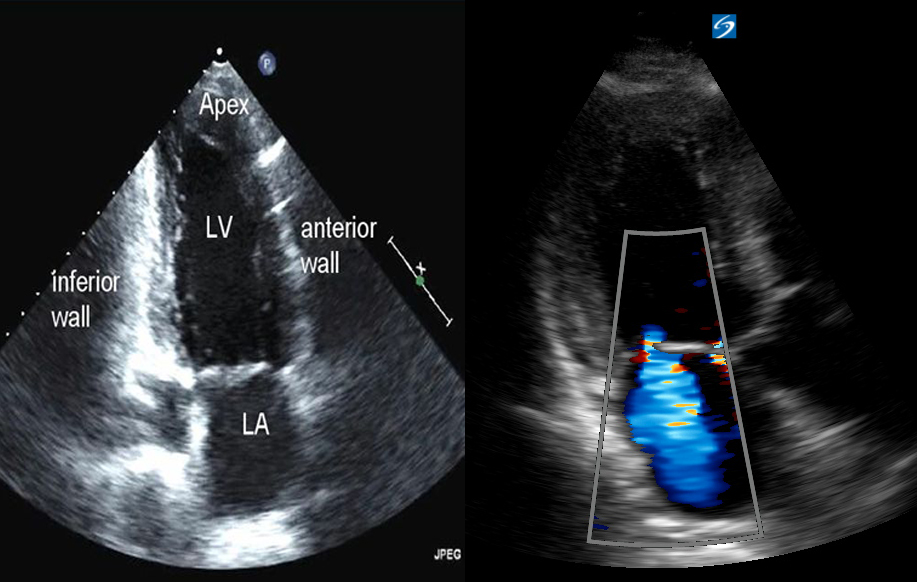

- Siêu âm hai chiều để kiểm tra những lát cắt về giải phẫu của tim (đem lại hình ảnh giải phẫu giống thực tế).

- Siêu âm Doppler gồm Doppler liên tục, Doppler tổ chức, Doppler màu,… giúp khảo sát các biến đổi về mặt hình thái, huyết động và các chức năng của tim.